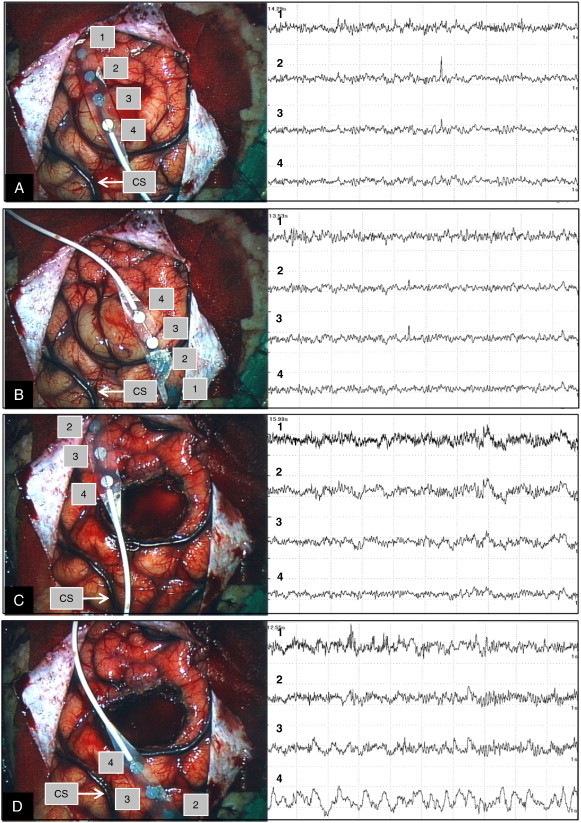

Fig. 2.

Case 1. Intraoperative ECoG prior to lesion resection showing interictal spikes, with representative ECoGs shown from different two sites (A and B). Epileptiform discharges which emerged on ECoG before lesion resection disappeared after lesion resection as shown on representative ECoGs from two different sites (C and D).

Fig. 5.

Case 2. Intraoperative ECoG before the lesion resection showing interictal spikes, and the representative ECoGs from two different sites (A and B). Epileptiform discharges which emerged on ECoG before lesion resection disappeared after lesion resection, and the representative ECoGs from two different sites are shown (C and D). CS = central sulcus.

Fig. 7.

Case 3. Intraoperative ECoG before lesion resection showing interictal spikes and the representative ECoGs from two different sites (A and B). Epileptiform discharges which emerged on ECoG before lesion resection disappeared after lesion resection on the representative ECoG (C).